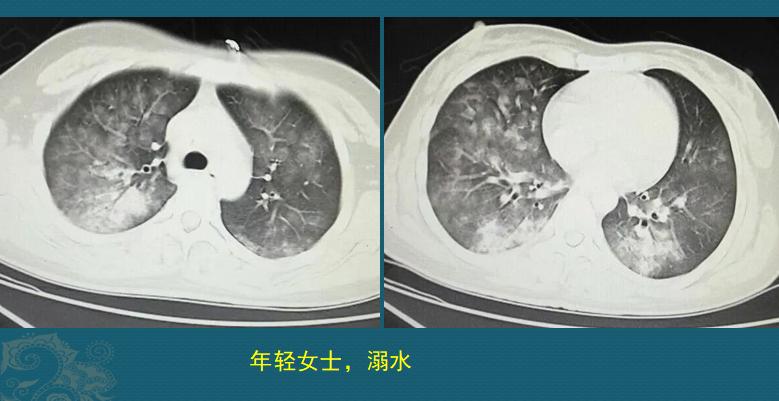

这是一位26岁女士,在人工湖游泳时溺水昏迷,呼吸、心跳停止,幸好被救生员及时发现,马上进行心肺复苏,呼吸心跳恢复,尽快送到医院,急诊CT发现双肺多发磨玻璃影,沿气道分布,部分肺实变(约溺水后2小时):

抢救溺水患者,时间就是生命!多亏救生员急救措施合理,时间没有耽搁,住院后经过吸氧、祛痰、消炎、保肝等治疗后很快好转,没有留下后遗症!上图是她住院第3天复查的CT,肺部磨玻璃影以一种很快的速度吸收了。